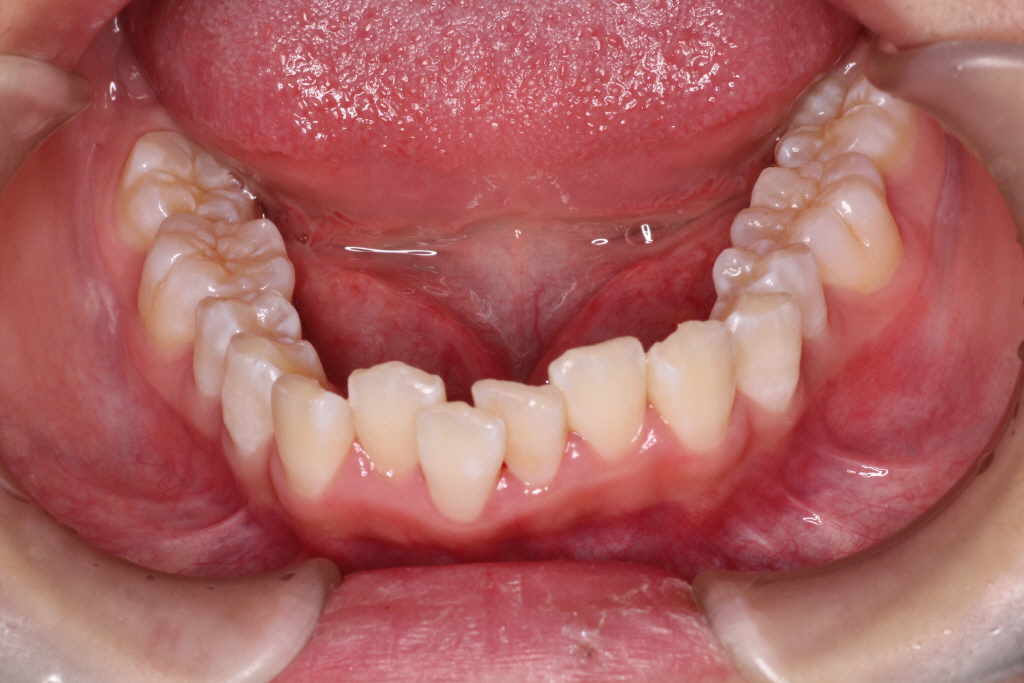

初診時の写真です。

前歯にはがたつき(叢生)がみられ、奥歯は上の歯と下の歯が1歯対1歯で噛んでいることがわかります。

つまり出っ歯の噛み合わせです。

診断:上顎前突・前歯部叢生